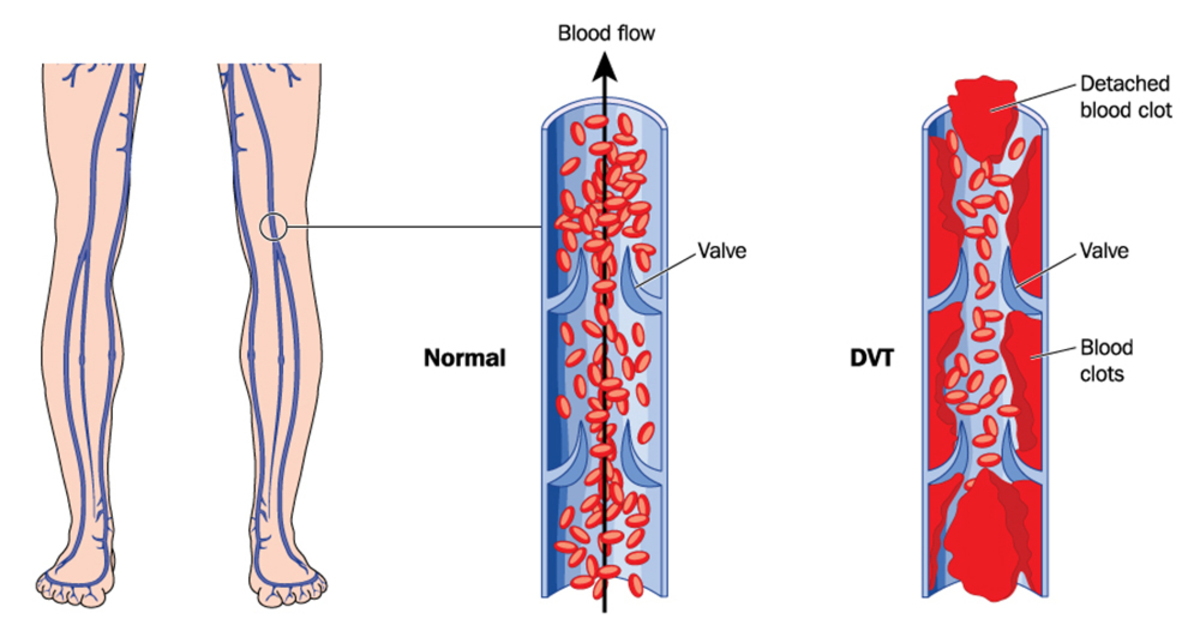

Φλεβική θρόμβωση οι ειδικοί την αποκαλούν και σιωπηλό δολοφόνο. Ποιοι κινδυνεύουν και τι πραγματικά συμβαίνει; Η φλεβική θρόμβωση συμβαίνει όταν ένας θρόμβος αίματος σχηματίζει σε μία ή περισσότερες από τις εν τω βάθει φλέβες του σώματός σας, συνήθως στα πόδια σας. Μπορεί να προκαλέσει πόνο στα κάτω άκρα ή πρήξιμο, αλλά μπορεί να εξελιχθεί και χωρίς συμπτώματα.

Η φλεβική θρόμβωση είναι μια σοβαρή κατάσταση. Θρόμβοι αίματος στις φλέβες σας μπορεί να αποσπαστούν από το σημείο που σχηματίστηκαν. Να “ταξιδέψουν” στο κυκλοφορικό σας σύστημα και να φτάσουν στους πνεύμονές σας. Εμποδίζοντας τη ροή του αίματος προς αυτούς (πνευμονική εμβολή).

Όταν τα πόδια σας παραμένουν ακίνητα για πολλές ώρες, οι μύες σας δεν συστέλλονται και αυτό οδηγεί κακή κυκλοφορία του αίματος. Θρόμβοι αίματος μπορούν να σχηματιστούν στις γάμπες των ποδιών σας, αν οι μύες της γάμπας σας δεν κινούνται για μεγάλες χρονικές περιόδους.